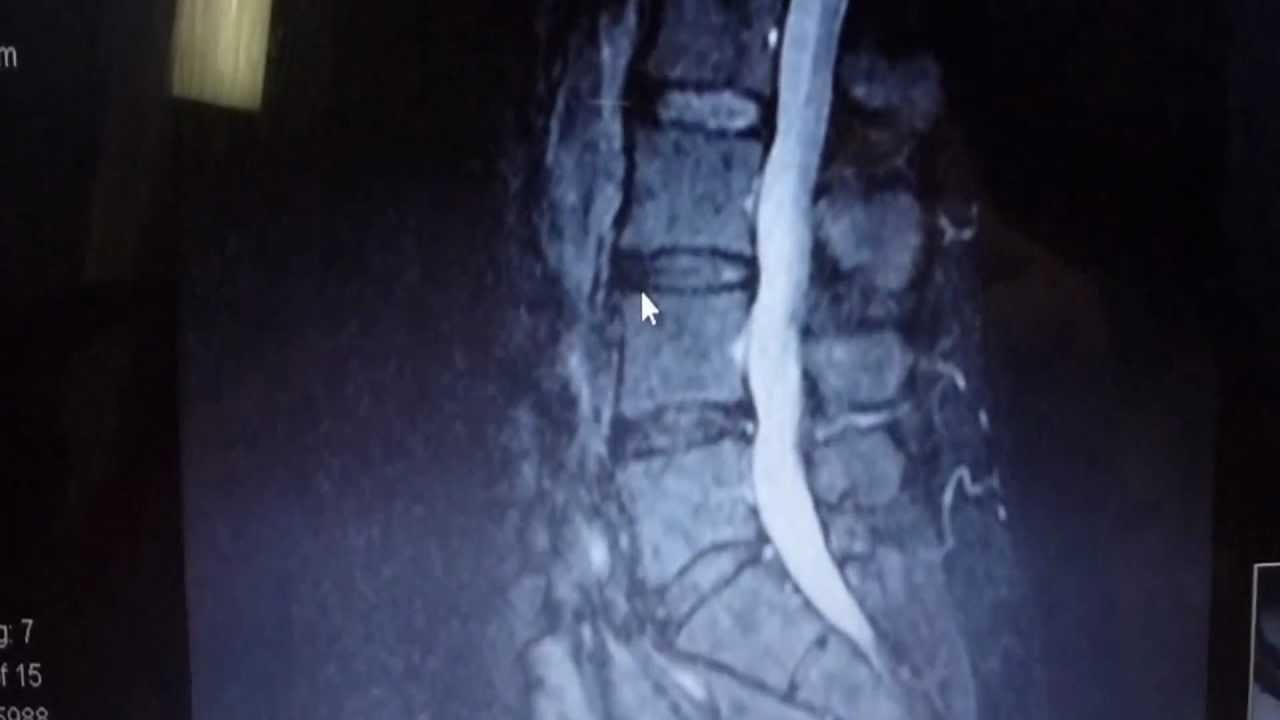

Spinal Decompression Demonstration at Advanced Chiropractic Relief

363 N Sam Houston Pkwy E Suite 1060 Houston Texas 77060 Spinal Decompression Demonstration at Advanced Chiropractic Relief By Your Houston Chiropractor Dr. Gregory Johnson. Advanced Chiropractic Relief located in North Houston next to George Bush Intercontinental Airport and across the street from the Hyatt North Houston Hotel. Please call (281) 405-2611 or visit us online at #houstonchiropractor #ringdinger #chiropractor #topchiropractor #bestchiropractor